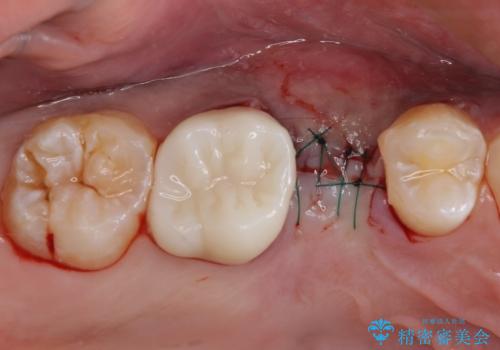

破折して抜歯が必要となった歯の後ろの歯は、根管治療が必要な状態であったので、根管治療を行い、矯正治療後にインプラント部の補綴治療と同時にセラミッククラウンを装着しました。

矯正治療以外に費用負担がかかることになりましたが、気になるところ全てを処置することができ、患者様には大変満足していただきました。